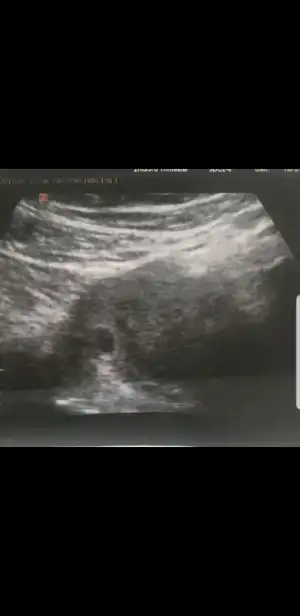

Merhaba hanımlar. Ne güzel haberler gelmiş pıt pıtlar duyulmuş. Bizim gelinin durumu hala belli değil. Salı günü biraz kanaması olmuş. Hemen doktora gitmiş. Doktor alttan bakmış. Gelişim yok bebekte yok demiş. P tesi gel kürtaja demiş. Bizim gelin de başka bir hastaneye gitmiş. Ordaki doktor kese düzgün kordon var demiş. Haftaya tekrar bakalım demiş. Aklı iyice karıştı. Kesenin ölçüsü yine yok.

Nedense ölçmüyorlar keseyi. Sat 20 eylül. Buna göre 7.hafta olması lazım. 5 haftalık demiş. Geçen haftada gittiğinde 5 haftalık demişlerdi.. ultrason görüntülerini yüklüyorum. Yorumlarınızı bekliyorum

Kesede oluşum görebildiniz mi ? Ben bakıyorum bakıyorum hiç bişey anlamıyorum. Pregestron iğne vurulmuş kanama başlayınca. Zaten günde 3 kere pregestron içiyordu. Kanama şuan yok. Günde 3 kere hapı bıraktırmış. Fitil olarak 1 kere vermiş